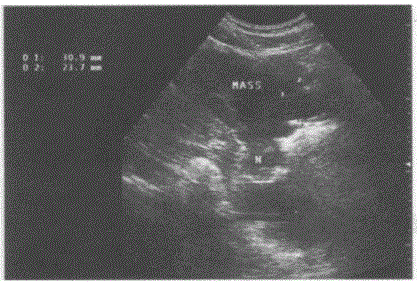

问题 临床资料:女,34岁,自述进食后上腹部不适。 超声综合描述:腹主动脉下腔静脉前方可见10.1cm×9.3cm形态不规则低回声,边界清晰,内回声不均匀,肝左叶受其推挤形态失常。 超声提示:

选项 A.胰腺癌 B.胃平滑肌肉瘤 C.肝癌 D.腹腔肿大淋巴结

答案 B